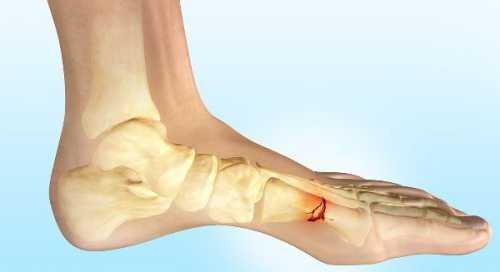

Имеются у пациента хронические заболевания опорно двигательного аппарата. Особенности профессиональной деятельности. Какие меры принимались для снятия болевых симптомов. Перелом пятой плюсневой кости, как и другие деформации стопы, требует обязательного проведения рентгено графического исследования. При необходимости вместо него используется компьютерная томография, показывающая не только деформацию костей, но и состояние мягких тканей и кровеносных сосудов. Врач всегда учитывает, что при стрессовых формах рентген не всегда указывает на патологию, так как она развивается внутри костной ткани, а поверхность остается целой. Терапия заболевания при этой травме может носить как консервативный, так и оперативный характер. Первый используется при закрытых переломах без смещения. При этом применяются мази, гели для снятия отеков, специальная диета и максимальный покой поврежденной конечности.

Оперативное вмешательство применяется при смещении отломков костей больше чем на половину диаметра или при открытых формах травмы. Оно заключается врепозиции отломков фиксации частей кости с помощью специальных винтов или пластин восстановлении или резекции кровеносных сосудовсшивании мягких тканей. Перелом плюсневой кости стопы после операции требует обязательного наложения гипсовой повязки. Ход лечения контролируется проведением периодических аппаратных исследований. После снятия гипса терапия переходит в реабилитационный период, цель которого полное восстановление функций опорно двигательного аппарата. Все процедуры проходят под контролем врача, что исключает получение осложнений. Перелом плюсневой кости стопы. Время выздоровления во многом зависит от тяжести травмы, особенностей организма пациента и его возраста. У пожилых людей восстановление костей происходит медленнее, чем у молодых. В то же время большое значение имеют различные заболевания, замедляющие заживление.